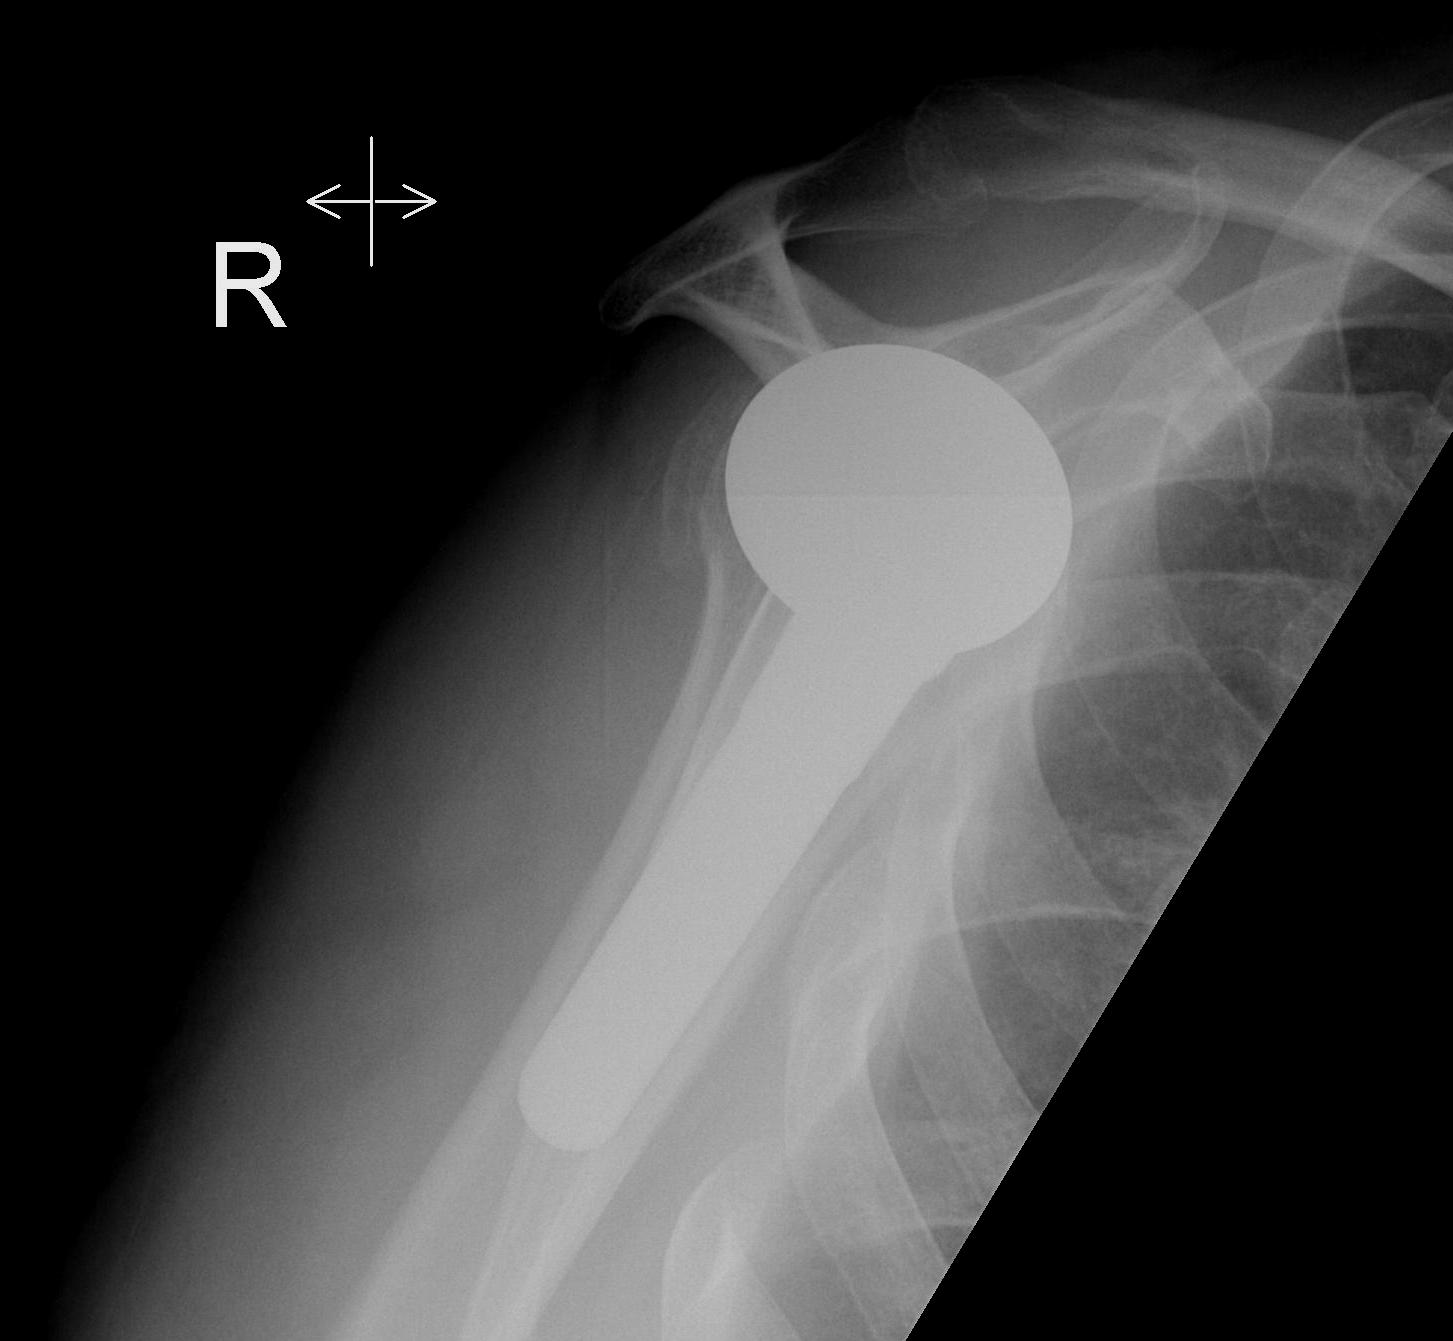

Humeral component

Modern components

Variety of thickness options of humeral head

- overstuffing of joint reduces ROM and places excessive stress on rotator cuff

Offset options

- normal head offset from neck posteriorly and medially

- placing head more anterior than normal can impinge on SSC and cause late rupture

Trial

Should be able to

A. Inferiorly sublux head 50% glenoid and return to center

B. Posteriorly sublux head 50% and return to center

C. Able to close subscapularis without impingement on head